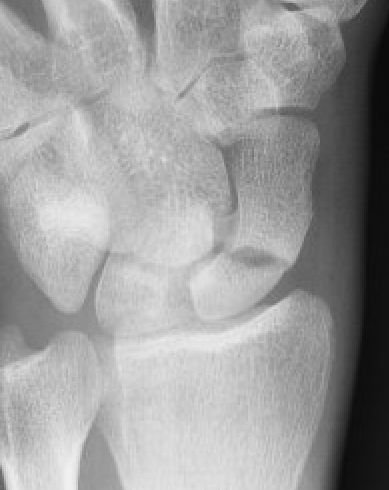

Xray

Increased sclerosis proximal pole consistent with AVN

Increased sclerosis proximal pole post surgery